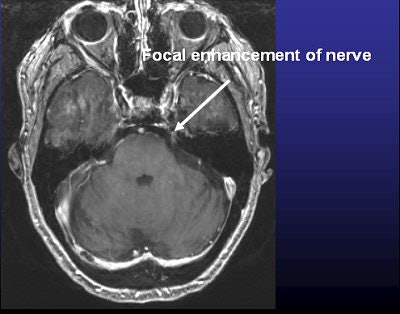

![]() |

| Above, frameless radiosurgery for TN. Below, three months after treatment. Images courtesy of Dr. Kevin Murphy and the University of California, San Diego, department of radiation oncology. |